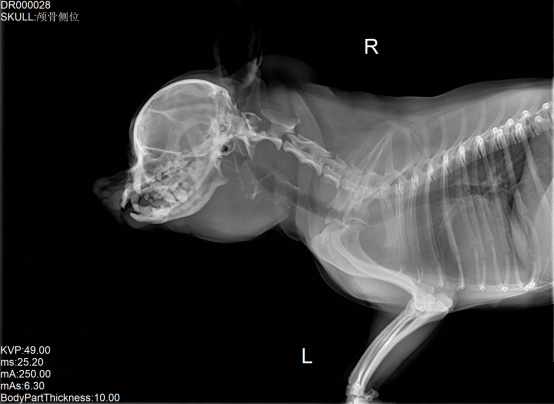

寵物DR是專業(yè)用于寵物X光拍攝的數(shù)字化X射線檢查,輔助寵物醫(yī)生進(jìn)行及時精確的診療。寵物DR主要包括五大主要部件,數(shù)字X光探測器,高壓發(fā)生器,球管,機架,寵物專用的DR工作站軟件。寵物DR由于采用數(shù)字技術(shù),自動成像處理,模擬X線圖像向數(shù)字化X線圖像的轉(zhuǎn)變。寵物DR與傳統(tǒng)模擬X光機相比有什么優(yōu)勢呢?采集時間10毫秒以下,成像時間僅為3秒,較高的空間分辨力和低噪聲率,提高了病灶的檢出率,避免漏診誤診等問題。減少X線對人體照射的不良影響寵物DR照片是您最佳的選擇。提高寵物醫(yī)生工作效率,總而言之,選擇寵物DR是寵物醫(yī)院的最佳選擇。寵物醫(yī)學(xué)影像學(xué)實現(xiàn)全數(shù)字化和無膠片化升級發(fā)展提高技術(shù)水平。